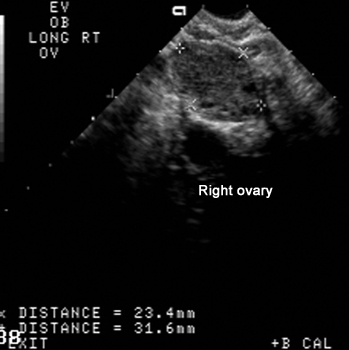

US Pelvis |

|